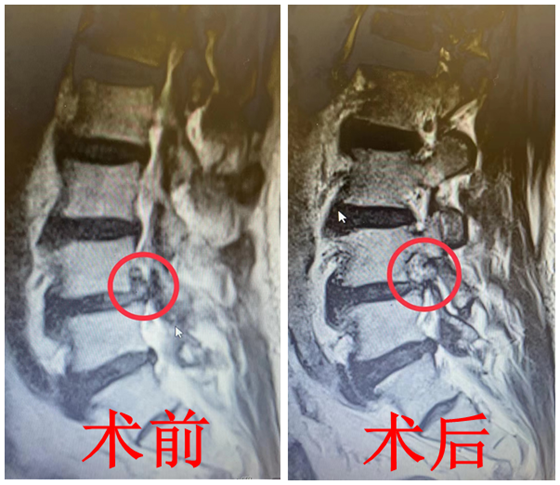

“痛在膝盖要命交,高人一看源自腰。精准一刀痛即消,唯有芳田医术高。”近日,湘雅常德医院骨科病房收到这样一幅特殊的锦旗。 “护士,护士,我膝盖疼了一晚上,...